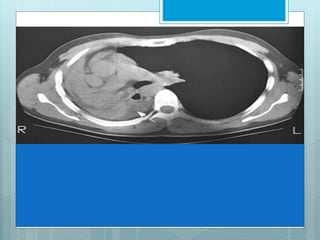

RLL Collapse

 Collapse is in post, med & inf

direction.

 Major fissure swings down

&backward.

 Hilum is displaced inferiorly.

 Hemidiaphragm is elevated.

 On PA view a triangular opacity

adjacent to spine with base on

hemidiaphragm.

 On lateral view there is

increased opacity over lower

thoracic vertebrae .

 Another indirect sign is vascular nodular sign, due to

compensatory hyperinflation of upper lobe.

 Radiographically seen as "hair-pin" turning of vessels &

"too-many nodules" along cardiac margin, which are end-on

vessels.